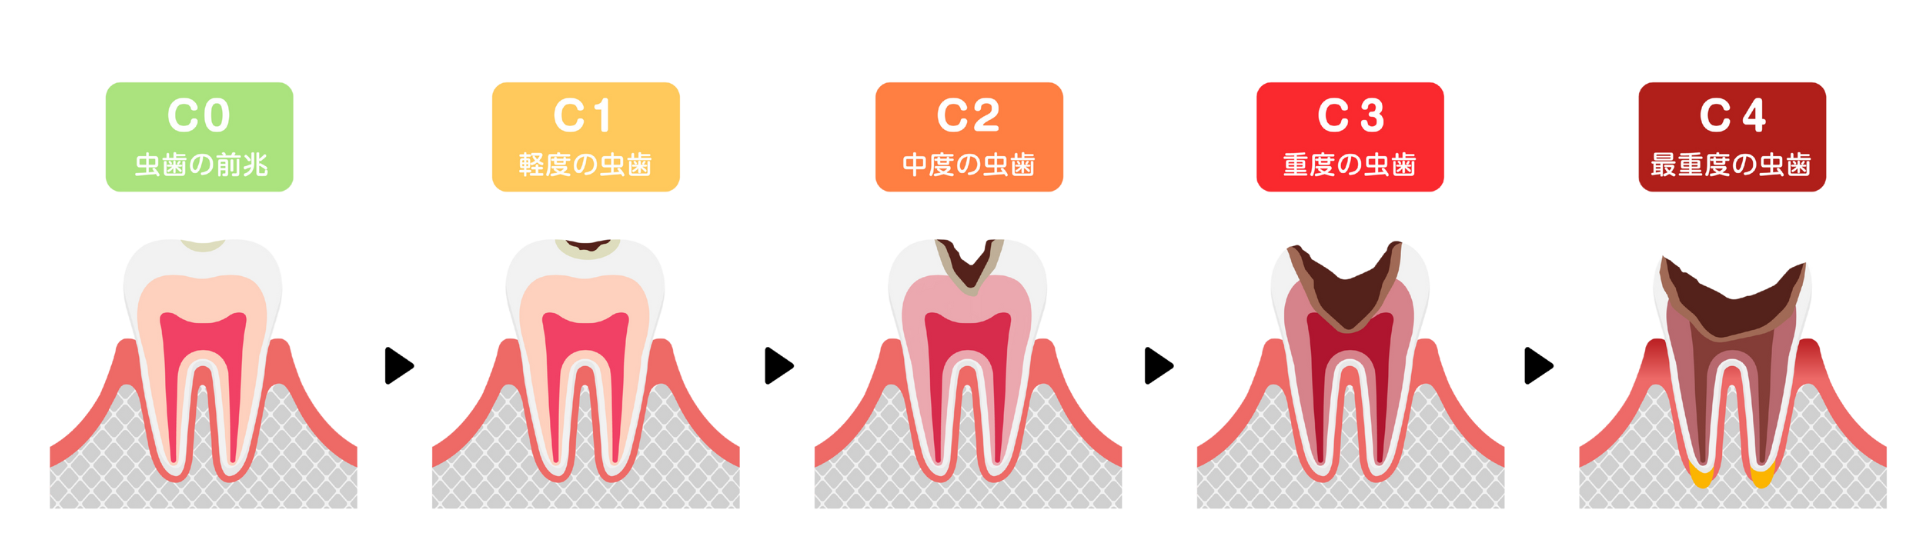

虫歯は進行度によってC0からC4までの段階に分けられます。

進行すればするほど治療は複雑になり、歯へのダメージも大きくなります。

| 段階 | 状態 | 症状 | 治療法 |

| C0:初期う蝕 | エナメル質が溶け始め、白く濁って見える状態 | 痛みなどの自覚症状は全くない | 適切な歯磨きやフッ素塗布などによる再石灰化 |

| C1:エナメル質う蝕 | エナメル質に小さな穴が開いた状態 | まだ痛みを感じることはほとんどない | 虫歯部分を最小限削り、レジンを詰める |

| C2:象牙質う蝕 | 虫歯が象牙質まで達した状態 | 冷たいものや甘いものがしみる | 詰め物(インレー)や被せ物(クラウン)で修復 |

| C3:神経まで達したう蝕 | 虫歯が歯髄(神経)にまで達した状態 | 何もしなくてもズキズキと激しく痛む | 根管治療(神経を取り除く治療) |

| C4:残根状態 | 歯の大部分が崩壊し、根っこだけが残った状態 | 激しい痛みは一旦なくなるが、膿が溜まって再び痛みや腫れ | 多くの場合、抜歯 |

早期発見・早期治療の重要性

このように虫歯は進行すればするほど歯に与えるダメージが大きくなり、治療にかかる時間や費用も増大します。そして何より一度削ったり抜いたりした歯は二度と元には戻らないのです。

ご自身の歯を生涯にわたって守るためには「C0」や「C1」といったごく初期の段階で虫歯を発見し、最小限の介入で治療を完了させることが極めて重要です。

そのためには痛みなどの自覚症状がなくても定期的に歯科医院で検診を受ける習慣が不可欠となります。